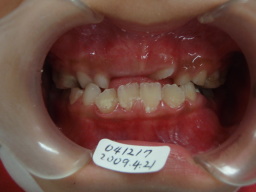

| 2009年04月17日(7才2ヶ月) 21番(左上切歯)がはえてきました。 反対咬合 第一大臼歯がまだはえてこない。 (固定源がない) |

| 2009年04月17日(7才2ヶ月) 第一大臼歯がまだはえてこない。 (固定源がない) 上顎乳臼歯(DE)にレジンを添加して咬合挙上 |